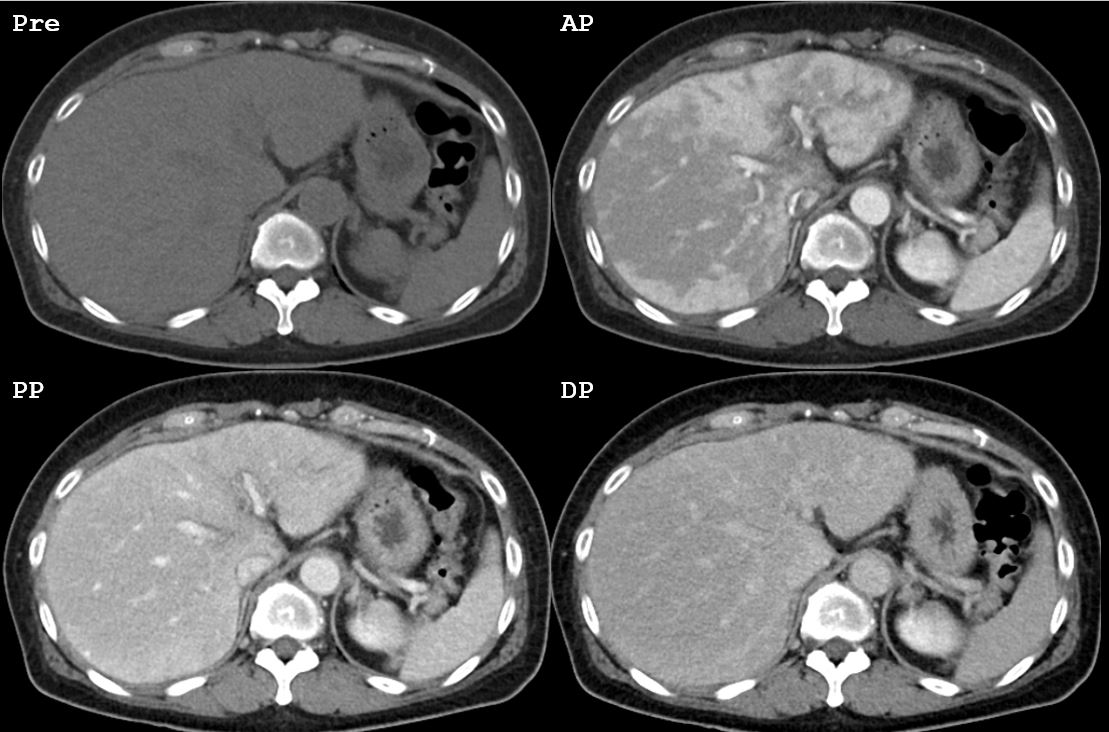

Case

No.728

M / 72

Heavy alcoholics, work up for liver tran...

ABDOMEN

¼¿ï¾Æ»êº´¿ø Á¤¿ëÁØ

CASE 1

5

2026-04-11